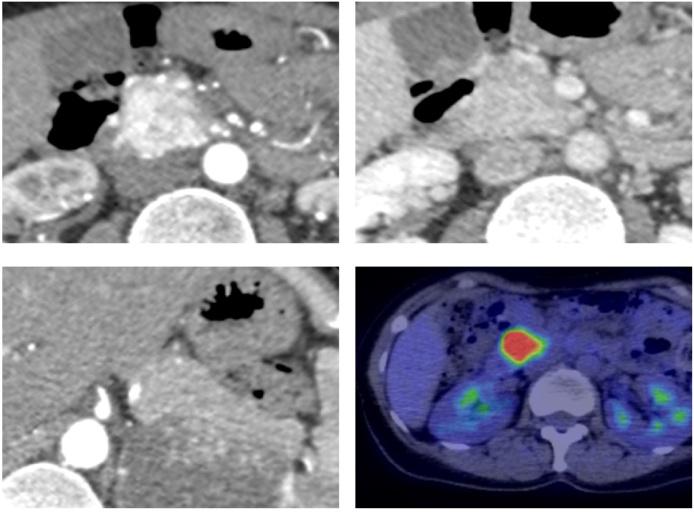

A 51-year-old woman presented with a cerebellar tumor, bilateral hypernephroma, and pancreatic tumor detected during a medical checkup. 18F-fluorodeoxyglucose positron emission tomography-computed tomography revealed a bilateral adrenal gland tumor and a tumor in the head of the pancreas, while an abdominal computed tomography examination revealed a 30-mm tumor with strong enhancement in the head of the pancreas. Cranial magnetic resonance imaging showed a hemangioblastoma in the cerebellum. Therefore, a diagnosis of vHL disease (type 2A) was made. Her family medical history included renal cell carcinoma in her father and bilateral adrenal pheochromocytoma and spinal hemangioblastoma in her brother. A detailed examination of endocrine function showed that the adrenal mass was capable of producing catecholamine. Treatment of the pheochromocytoma was prioritized, and therefore, laparoscopic left adrenalectomy and subtotal resection of the right adrenal gland were performed. Once the postoperative steroid levels were replenished, subtotal stomach-preserving pancreatoduodenectomy was performed for the PNET. After a good postoperative course, the patient was discharged in remission on the 11th day following surgery. Histopathological examination findings indicated NET G2 (MIB-1 index 10-15%) pT3N0M0 Stage II A and microcystic serous cystadenoma throughout the resected specimen. The patient is scheduled to undergo treatment for the cerebellar hemangioblastoma.

一名51岁女性在体检时发现小脑肿瘤、双侧肾肿瘤和胰腺肿瘤。18F-氟脱氧葡萄糖正电子发射断层扫描-计算机断层扫描显示双侧肾上腺肿瘤和胰头肿瘤,而腹部计算机断层扫描检查显示胰头有一个30毫米的肿瘤,强化明显。头颅磁共振成像显示小脑有血管母细胞瘤。因此,诊断为2A型vHL病。她的家族病史包括父亲患肾细胞癌,哥哥患双侧肾上腺嗜铬细胞瘤和脊髓血管母细胞瘤。详细的内分泌功能检查显示肾上腺肿块能够产生儿茶酚胺。优先治疗嗜铬细胞瘤,因此,进行了腹腔镜左肾上腺切除术和右肾上腺次全切除术。术后补充类固醇水平后,对PNET进行了保留胃的胰十二指肠次全切除术。术后恢复良好,患者在术后第11天缓解出院。组织病理学检查结果显示为NET G2(MIB-1指数10-15%)pT3N0M0 II A期,整个切除标本为微囊性浆液性囊腺瘤。患者计划接受小脑血管母细胞瘤的治疗。